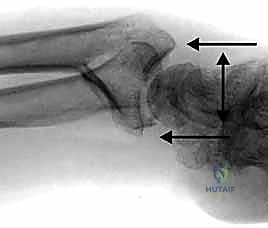

- الأشعة السينية (X-rays):

هي الخطوة الأولى لتقييم الكسر. يتم أخذ صور من زوايا متعددة (أمامية خلفية، جانبية، ومائلة) لتحديد موقع الكسر الأساسي ودرجة الانزياح والتقصير في عظم الكعبرة.

- التصوير المقطعي المحوسب (CT Scan) مع إعادة البناء ثلاثي الأبعاد:

هذا هو المعيار الذهبي الذي يعتمده الدكتور هطيف لجميع كسور المفصل المعقدة. تتيح الأشعة المقطعية رؤية كل شظية عظمية بوضوح تام، وتحديد حجمها، وموقعها، ودرجة تفتت السطح المفصلي بدقة ملليمترية. من خلال إعادة البناء ثلاثي الأبعاد (3D Reconstruction)، يمكن للدكتور هطيف "رؤية" الكسر من جميع الزوايا قبل فتح الجلد، مما يسمح له باختيار الغرسات (الصفائح والمسامير) الدقيقة لكل شظية وتحديد المداخل الجراحية المثلى.